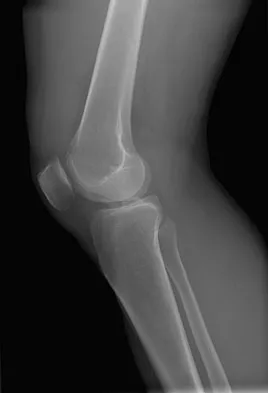

Figures 5a and 5b show the radiographs of an 11-year-old boy who felt a pop and immediate pain in his right knee as he was driving off his right leg to jam a basketball. Examination reveals that the knee is flexed, and the patient is unable to actively extend it or bear weight on that side. There is also a large effusion. Management should include

Explanation

Fractures through the cartilage on the inferior pole of the patella, the so-called sleeve fracture, are often difficult to diagnose because of the paucity of ossified bone visible on the radiographs. If the fracture is missed and the fragments are widely displaced, the patella may heal in an elongated configuration that may result in compromise of the extensor mechanism function. The treatment of choice is open reduction and internal fixation using a tension band wire technique to achieve close approximation of the fragments and restore full active knee extension. Heckman JD, Alkire CC: Distal patellar pole fractures: A proposed common mechanism of injury. Am J Sports Med 1984;12:424-428.